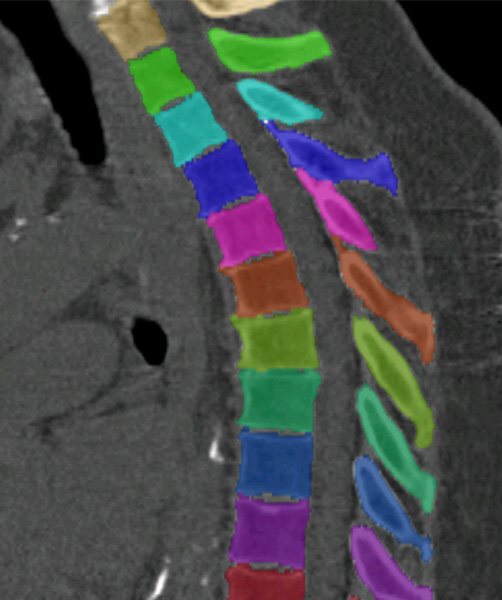

We trained and evaluated the method with five sets of CT and MR scans that visualize the spine. Reference segmentation masks for four of these datasets are publicly available, which allowed for a comparison with other publications that used the same data. Examples of images from the datasets are shown in Figure 3.

Similar performance was achieved for vertebra segmentation in various CT datasets with an average Dice score of and for vertebral body segmentation in an MR dataset with an average Dice score of . Surface distances were lower on CT images compared to MR images ( vs. ), however, there were also fewer training scans available in the MR dataset. Figure 4 illustrates the magnitude of differences of the automatic segmentations from the ground truth segmentations.

(a) Low-dose chest CT

(b) Lumbar spine CT (xVertSeg.v1 dataset)

(c) Lumbar spine MR

In the CT datasets, the segmentation was more accurate on high-resolution dedicated spine scans of healthy subjects compared with low-dose low-resolution chest CT scans and scans of subjects with in some cases severe compression fractures. This is also visible in the segmentation performance stratified by vertebra (Figure 5). Segmentations were more accurate for the lumbar (L1-L5) than for the thoracic vertebrae (T1-T12), which are covered by the more challenging low-dose chest CT scans. Outliers among the lumbar vertebrae correspond to vertebrae from the xVertSeg.v1 dataset, which features a number of severely deformed lumbar vertebrae that are particularly challenging to segment.